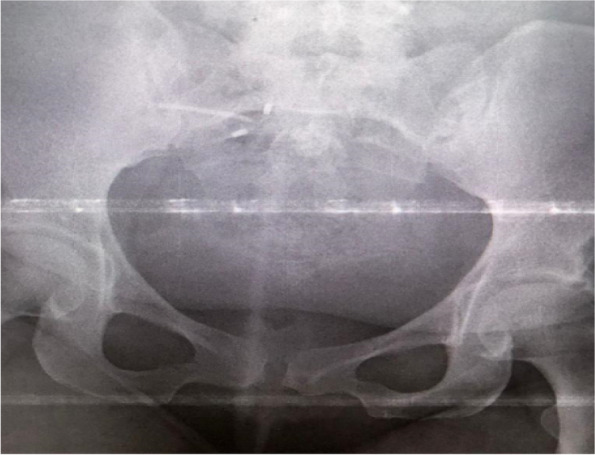

Background: Loss of Intra Uterine Device (IUD) following silent perforation of the uterus either during or after IUD insertion is an uncommon finding due to a lack of immediate follow-up. We report a rare case in which uterine perforation following the migration of IUD to the right fallopian tube without visceral injury. The patient presented with lower abdominal pain and pain during sex for one year since IUD insertion. On examination, we noted tenderness on the right suprapubic region and on speculum examination, no IUD thread was seen. A radiological pelvic examination showed an empty uterus without an IUD. Laparotomy and retrieval of migrated IUD was done followed by repair of perforated uterus.

Abstract Image